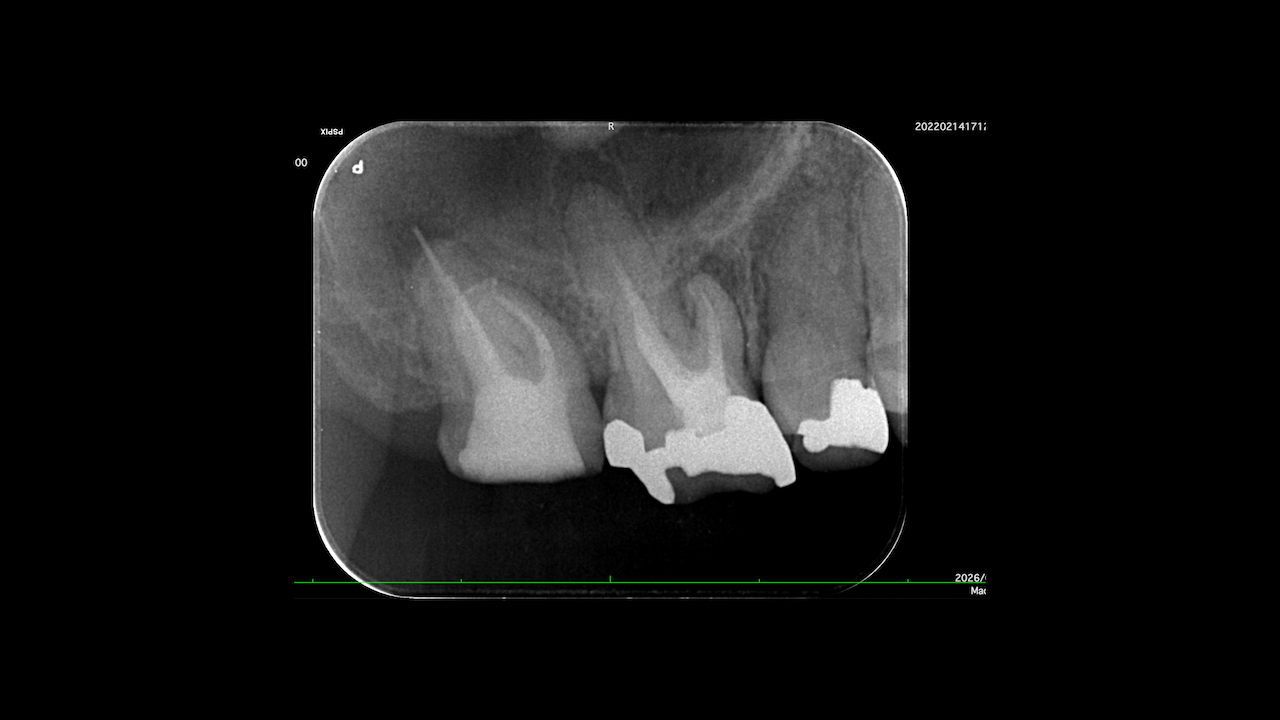

Sinus tractがある歯牙の再根管治療だ。

DB根はすでに切断されている。

が、逆根充がなされていない。

DBは根切済みだ。

Pにも病変がある。

ということは、再根管治療だろう。

ただ、予後はGuardedだ。

なぜか?根切がうまく行っていないからだ。

臨床的にDB

この後、

Sinus tractは消失した。

3ヶ月経過した。

DBの病変が小さくなっている。

Pは病変が大きくなっていうように見えるがまだわからない。